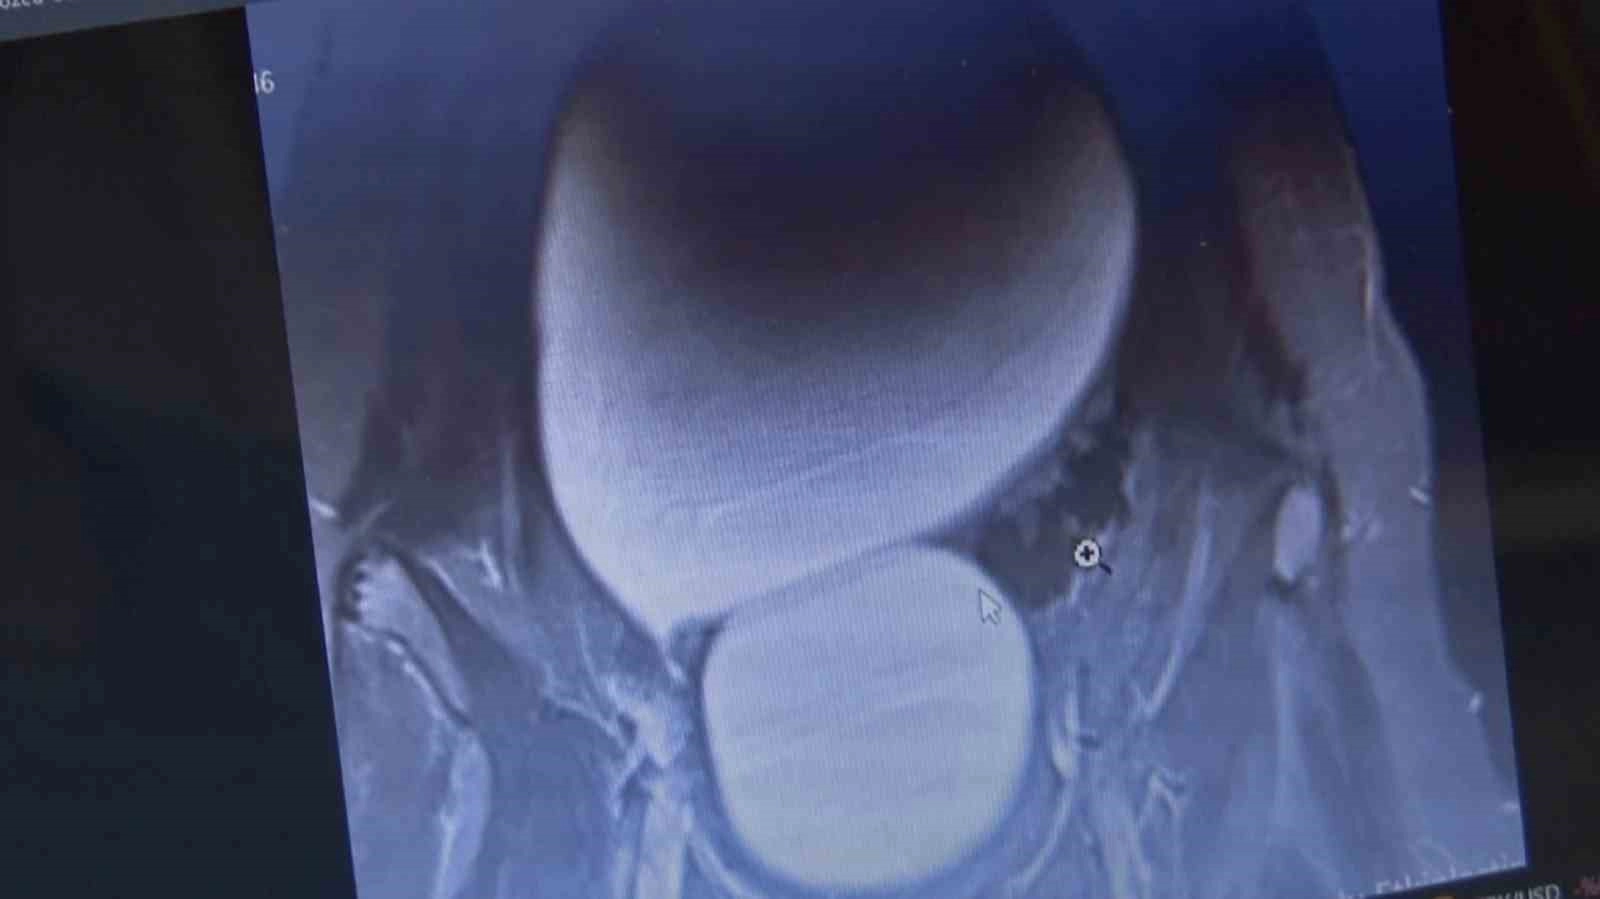

Sivas’ta yaşayan 12 yaşındaki genç kızın karın bölgesinde bulunan kavun büyüklüğündeki kist başarılı operasyonla çıkarıldı.Sivas’ta yaşayan 12 yaşındaki N.B. şiddetli karın ağrıları ve düzensiz adet kanamaları şikayetiyle hastaneye başvurdu. Yapılan detaylı tetkikler sonucunda genç kızın karın bölgesinde yaklaşık 25 santimetre çapında adeta kavun büyüklüğünde bir kist olduğu tespit edildi. Medicana Sivas Hastanesi’nde Çocuk Cerrahisi Uzmanı Op. Dr. Mahmut Aluç tarafından gerçekleştirilen başarılı bir operasyonla, genç kızın sol yumurtalığında bulunan ve karaciğere kadar uzanan devasa kist içerisindeki 1.6 litre su boşaltılıp, başarıyla çıkarıldı. Sağlığına kavuşan genç kız taburcu edildi.Operasyon sırasında kistten yaklaşık 1.6 litre sıvı boşaltıldıÇocuk Cerrahisi Uzmanı Op. Dr. Mahmut Aluç, kisttin içerisinden yaklaşık 1.6 litre sıvı boşaltıldığını söyleyerek, “ Karın ağrısı, düzensiz adet şikayetiyle bize geldi. Dışarıda yapan tetkiklerde ve bizde yapılan tetkiklerinde karın içerisinde yaklaşık yirmi beş santimetrelik çapında bir kitli kitle tespit ettik. Burada da tetkiklerimize tekrar baktığımızda sol över kökenli bir kisttik yapı olduğunun farkına vardık. Gerekli incelemeleri yaptıktan sonra ve ailenin onayını aldıktan sonra hastayı operasyona aldık. Karaciğere kadar uzanan bir kisttik yapımız vardı. Onun içerisinde yaklaşık 1.6 litre sıvı boşalttık. Over dokusunu, yumurtalık dokusunu koruyarak kisti tamamen eksize ettik. Hastamızı şifayla taburcu ettik. Patoloji sonucumuz da iyi huylu olarak geldi” dedi.“İlk adetin başladığı ergenlik çağında olan overkistlerin daha yakın takip edilmesi lazım”Adetin başladığı ergenlik çağında olan overkistlerin yakından takip edilmesi gerektiğine değinen Aluç, “ Çocuklarda özellikle ergenlik çağında bu tür semptomlar, karın ağrısı, adet düzensizliği olduğu zaman mutlaka ebeveynler çocuklarını muayeneye getirmeleri lazım. Bir yenidoğan döneminde bir de çocuklarda ergenlik döneminde yumurtalık kistlerine daha fazla rastlıyoruz. Yenidoğan döneminde olanlar anneden geçen östrojen kaynaklı oluyor ve genellikle kendiliğinden kayboluyor. Ama ilk adetin başladığı ergenlik çağında olan overkistlerin daha yakın takip edilmesi lazım. Bunlarda kistin boyutu beş santimetrenin üzerine çıkarsa over torsiyonu dediğimiz overin kangren olma durumu olduğu için yakın takip edilmesinde büyük fayda var” diye konuştu.